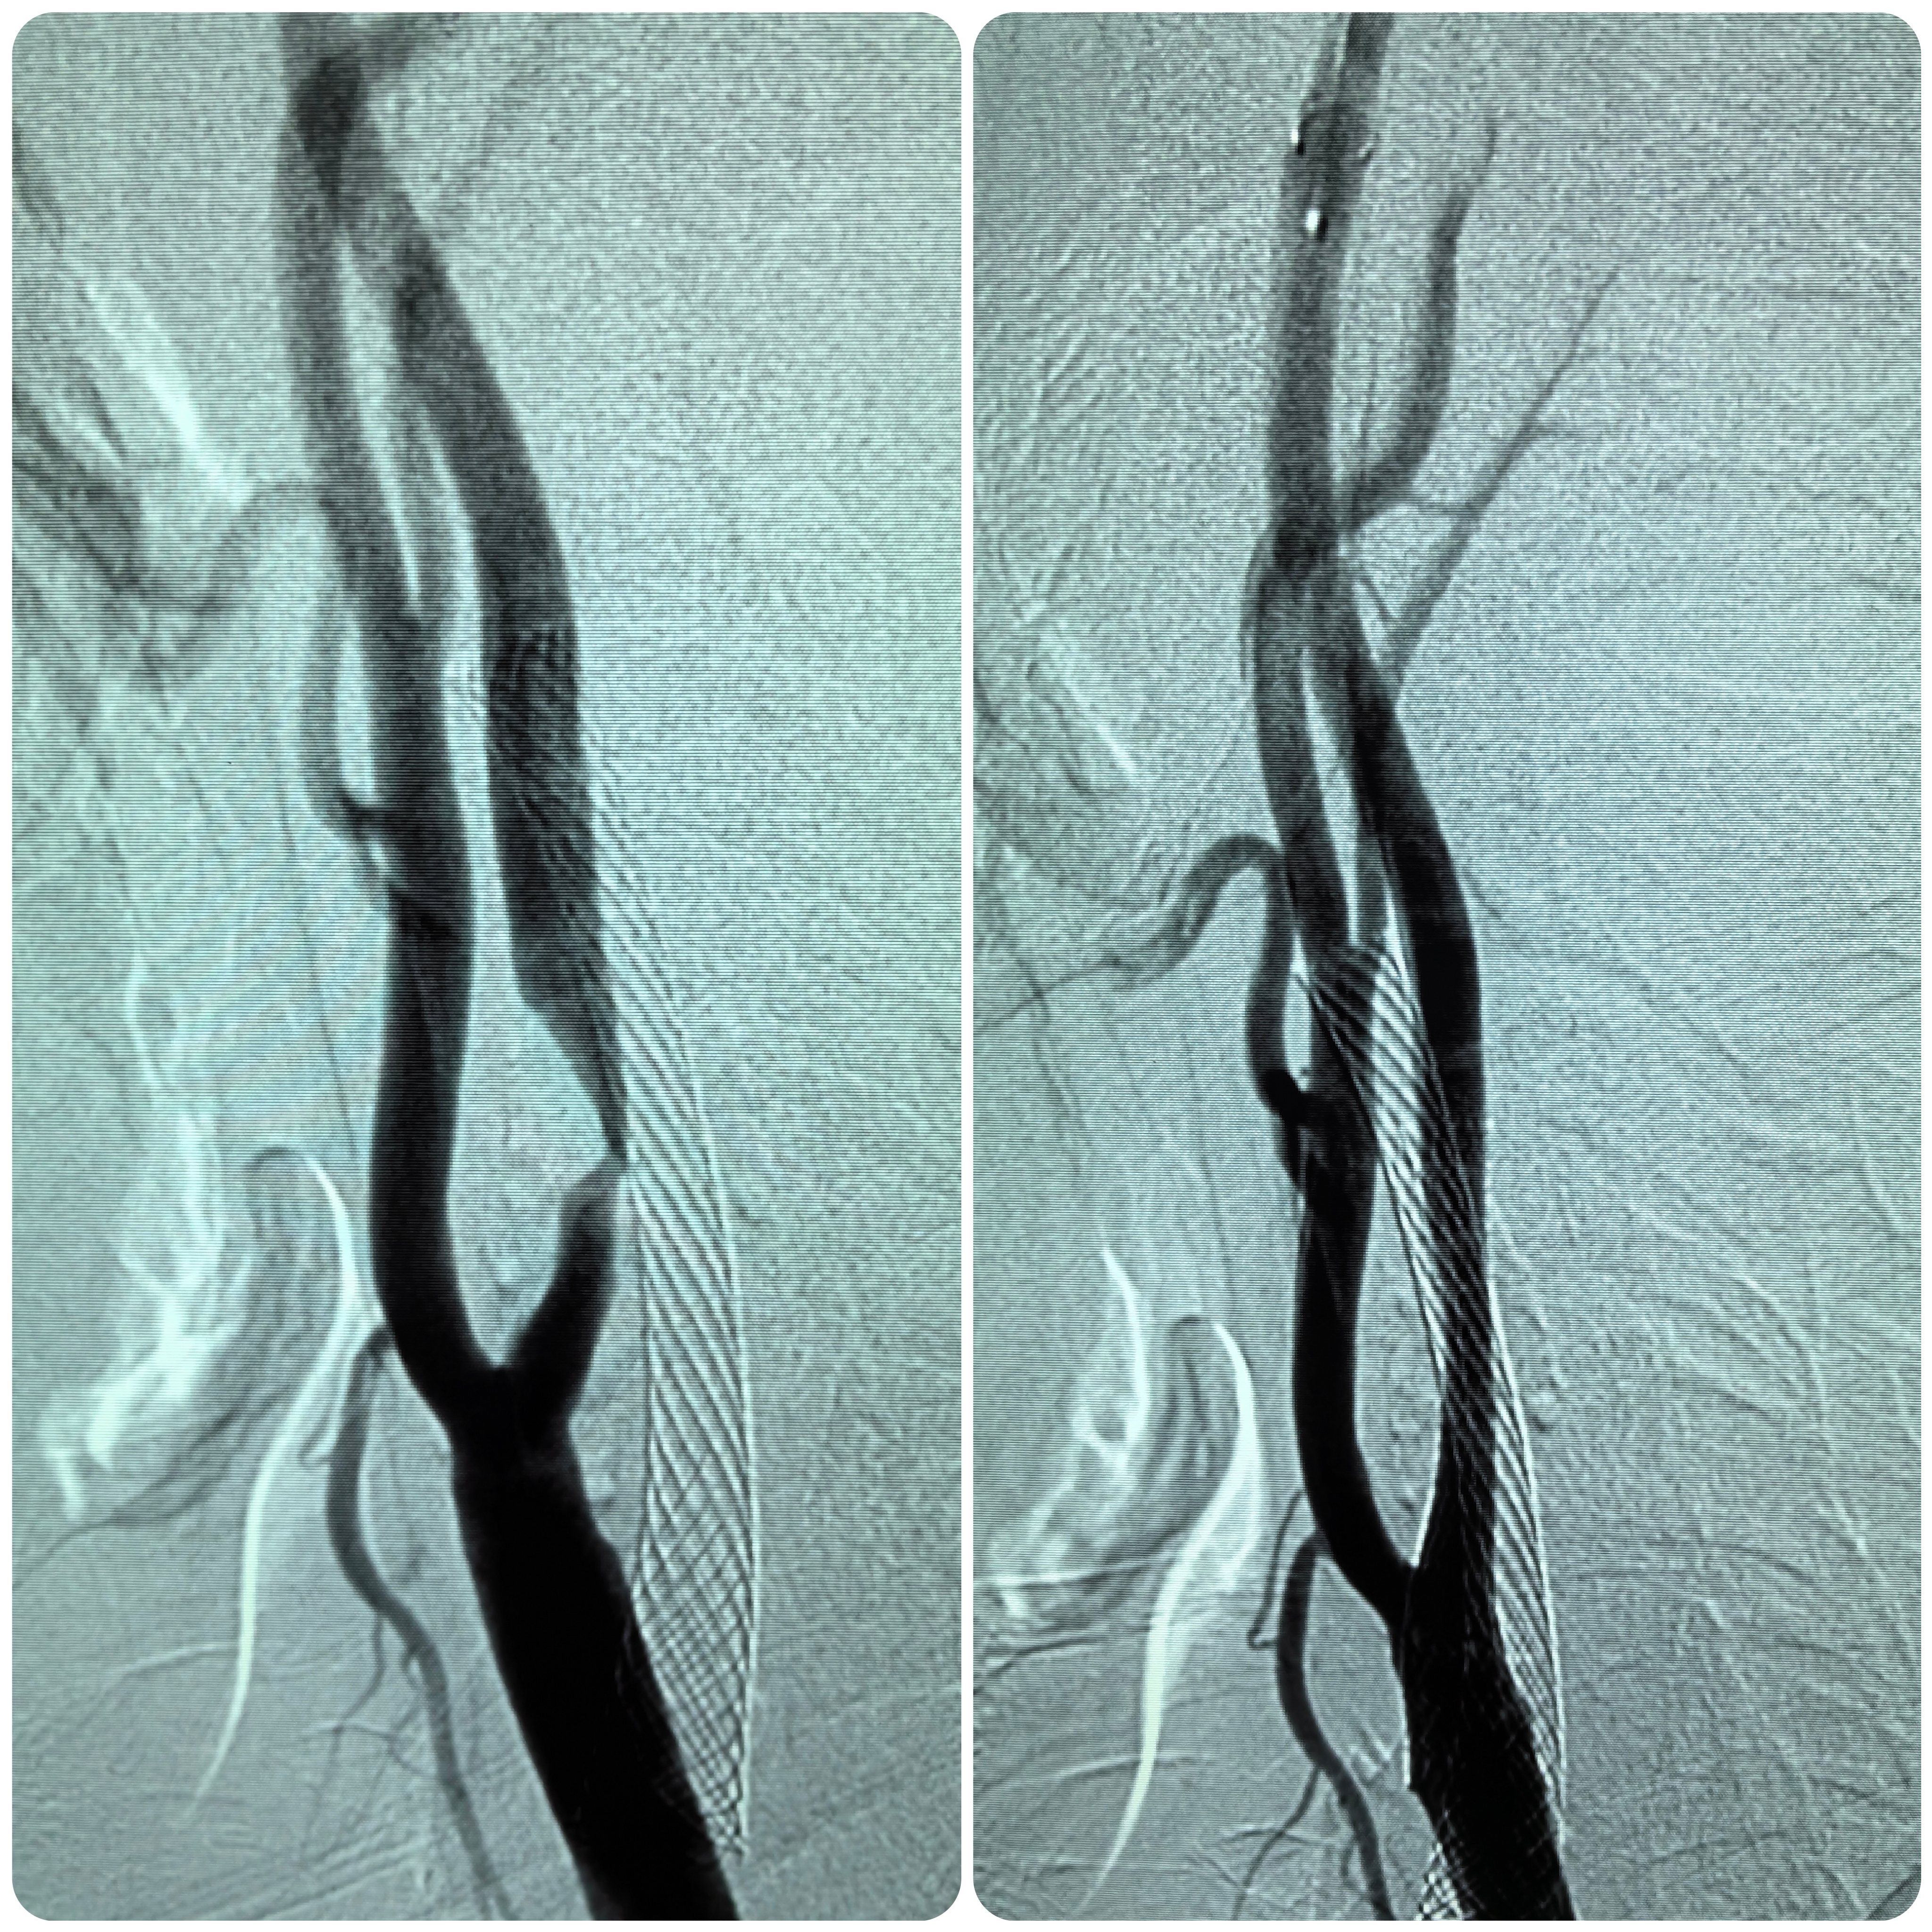

患者男性,70岁,体检发现双侧颈内动脉重度狭窄,1月前行右侧颈内动脉支架成形术,现为治疗左侧颈内动脉狭窄入院。既往高血压病史30年,口服硝苯地平控释片降压,血压控制130/80mmHg。

1、本例患者老年男性,双侧颈内动脉重度狭窄,治疗采取分期处理,间隔4周。

2、左侧颈内动脉从CTA看狭窄合并软斑,具备介入治疗指征。